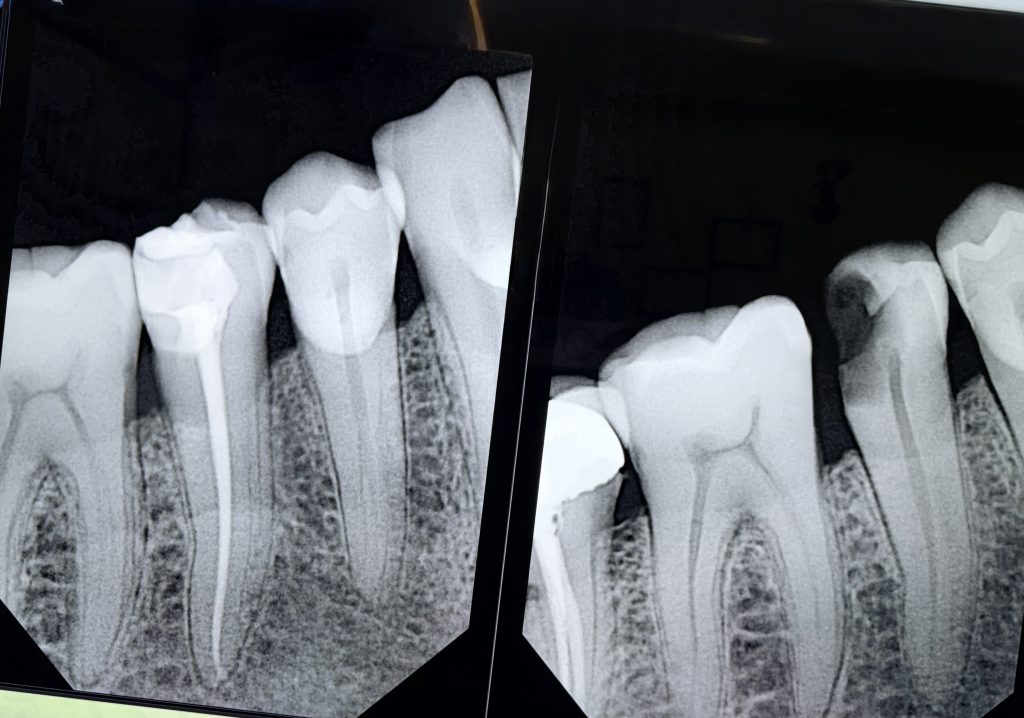

The canal was obturated using a bioceramic sealer (EndoSequence BC Sealer) with single-cone hydraulic technique (Fig 3). The sealer’s bioactivity ensured a hermetic apical seal and bonding compatibility with resin composites.

The final restoration showed ideal contour, proximal contact, and occlusal harmony (Fig 8). Radiographic review confirmed dense obturation and perfect coronal seal. At 1-month follow-up, the tooth remained asymptomatic and functional.

- Fig 3: Canal obturation with bioceramic sealer.

- Fig 8: Final radiograph and clinical outcome showing functional integration.